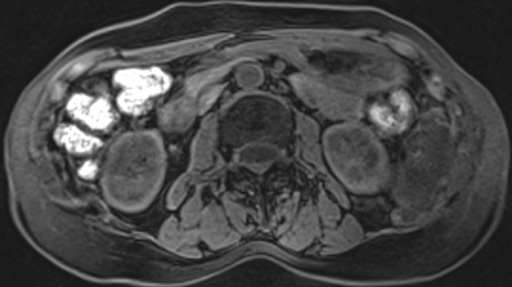

(左腎門部レベル) 図3 左:T1強調横断像

図3 左:T1強調横断像

(in-phase) 図4 T1強調横断像

図4 T1強調横断像

(out-of-phase) 図5 T2強調横断像

図5 T2強調横断像 図6 拡散強調横断像(b=1000)